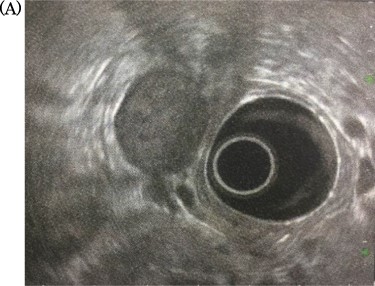

A 69-year-old woman presented to our institution with right abdominal pain. There was nothing special to mention in her family history. Her past medical history included horseshoe kidney, gastric ulcer, and asthma. Physical examination revealed a slight tenderness of the right quadrant abdomen. All laboratory parameters including the tumor markers carcinoembryonic antigen and carbohydrate antigen 19-9 were within normal limits. Abdominal ultrasonography showed a regularly shaped uniform tumor of about 50 mm in diameter that was located in the right retroperitoneum ventral to the right part of the horseshoe kidney. The tumor was hypervascularized (Fig. 1). Computed tomography (CT) showed a tumor of 80 mm in diameter ventral to the right part of the horseshoe kidney and the dorsal side of the descending part of the duodenum. On contrast-enhanced CT, the tumor showed late-phase enhancement. There were no findings of invasion into any organs and right ovarian vein ran through the tumor (Fig. 2). No metastases to organs or swollen lymph nodes were found. Magnetic resonance imaging (MRI) showed a tumor that was isointense with respect to muscle on T1-weighted images and of high-signal intensity on T2-weighted images (Fig. 3). No fatty components were detected in the tumor. Endoscopic ultrasonography showed a regularly shaped and hypoechoic tumor with no connection to the right part of the horseshoe kidney or duodenum (Fig. 4). Our working diagnosis was a retroperitoneal tumor that could be either a malignant lymphoma, leiomyoma or gastrointestinal stromal tumor.

Endoscopic ultrasonography: there was no finding of infiltration to the right kidney and the duodenum.